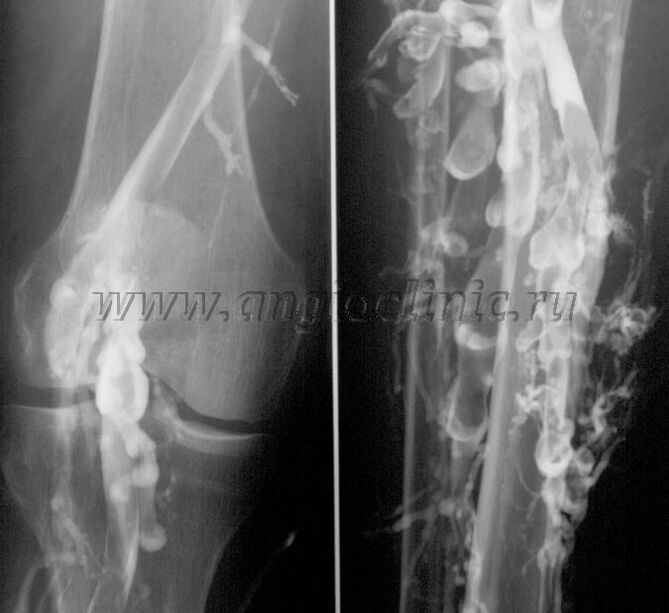

Venografie cu contrast

De obicei, scanarea cu ultrasunete este suficientă pentru un diagnostic complet al patologiei venoase, dar în unele cazuri este necesar să se studieze relația dintre starea sistemului venos profund și superficial, mai ales în cazul recidivelor varicelor și varicelor secundare.

Pentru a rezolva aceste probleme, se utilizează examinarea cu raze X de contrast. Venele safene sunt perforate si se administreaza contrast. Mișcarea contrastului este observată pe monitorul aparatului cu raze X și se efectuează toate testele și proiecțiile necesare. În prezent, venografia pentru vene varicoase este folosită foarte rar.